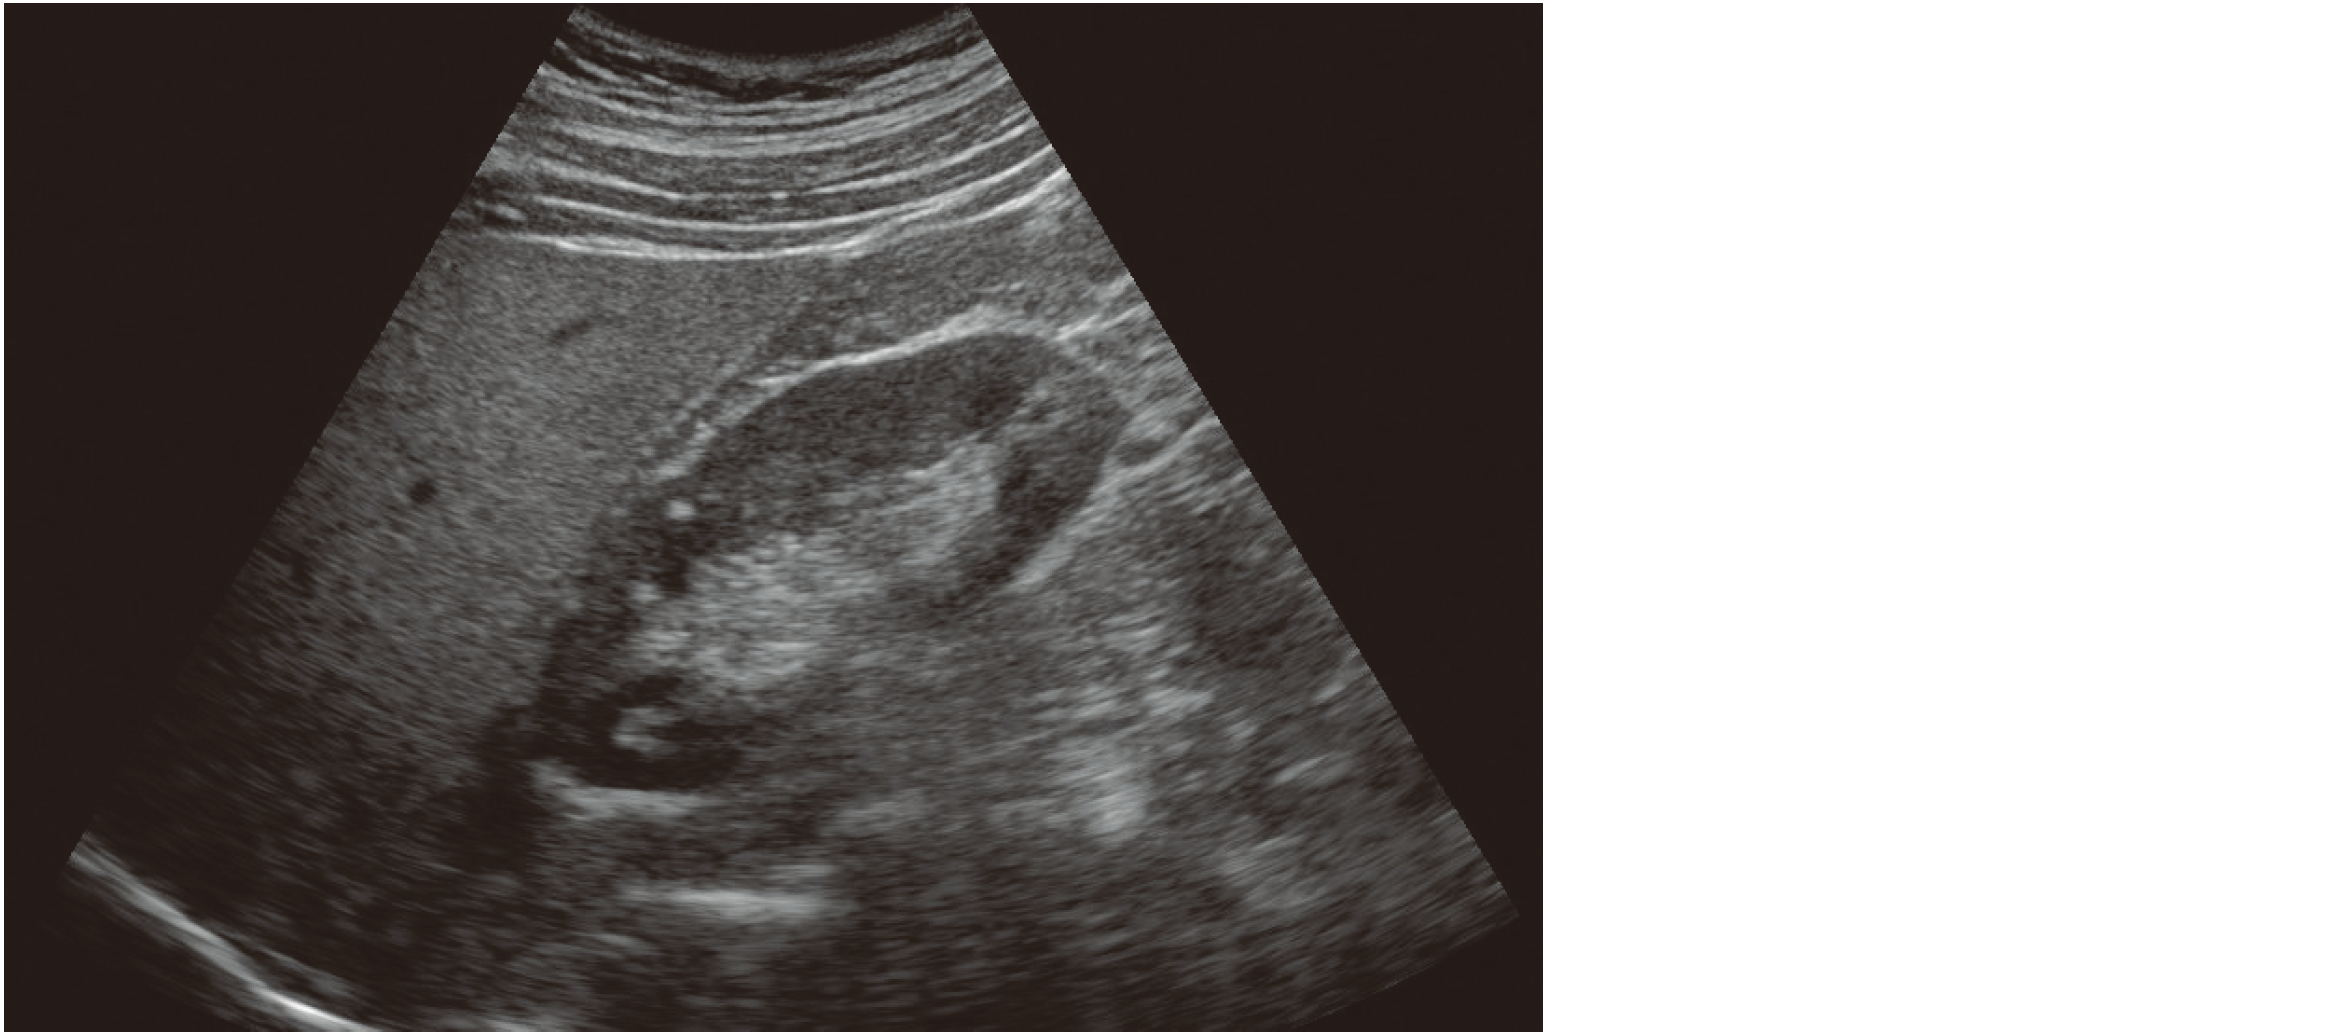

右季肋部縦走査による超音波像を示す。

所見はどれか。

• 1. 肝表面不整

• 2. カメレオンサイン

• 3. ブルズアイサイン

• 4. モザイクパターン

• 5. 肝腎コントラストの増強